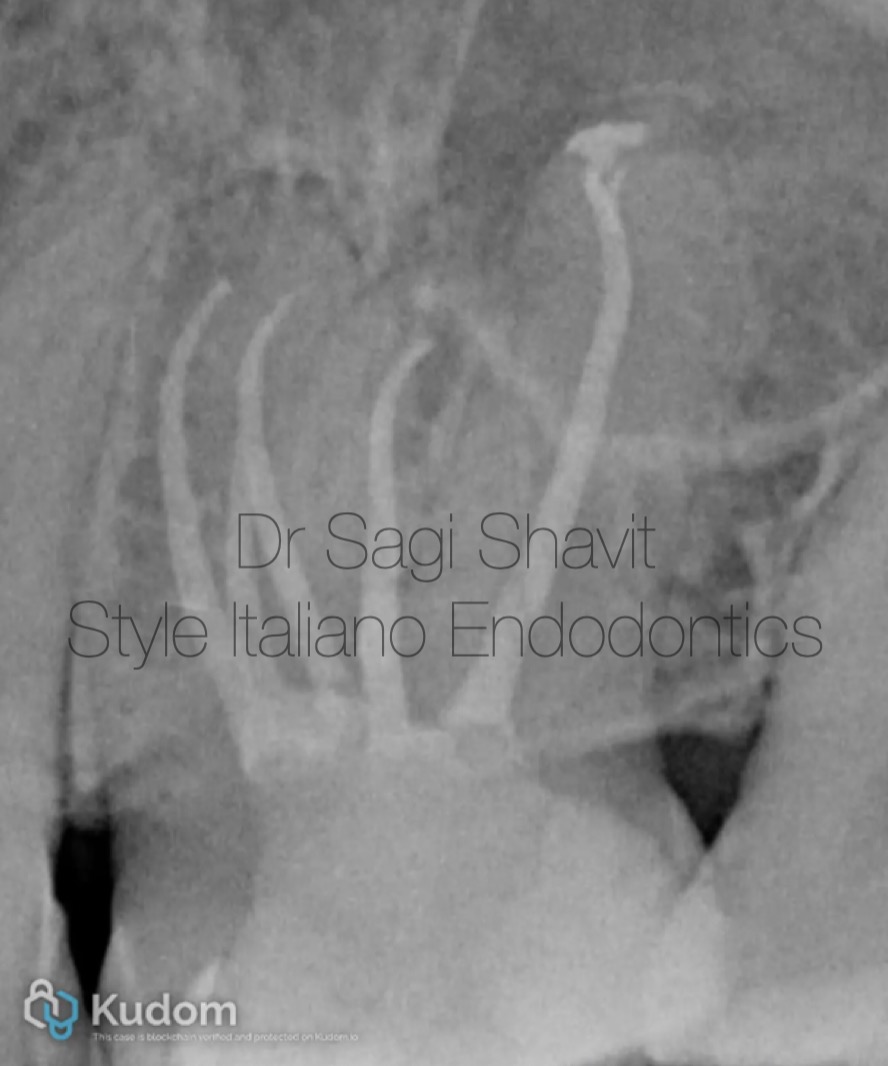

This UL6 (26) presented with irreversible pulpitis, and pulp canal obliteration.

Fig. 2

An investigation of a groove in the MB root, using fine ultrasonic tip reveals the presence of MB2 and MB3 canals.